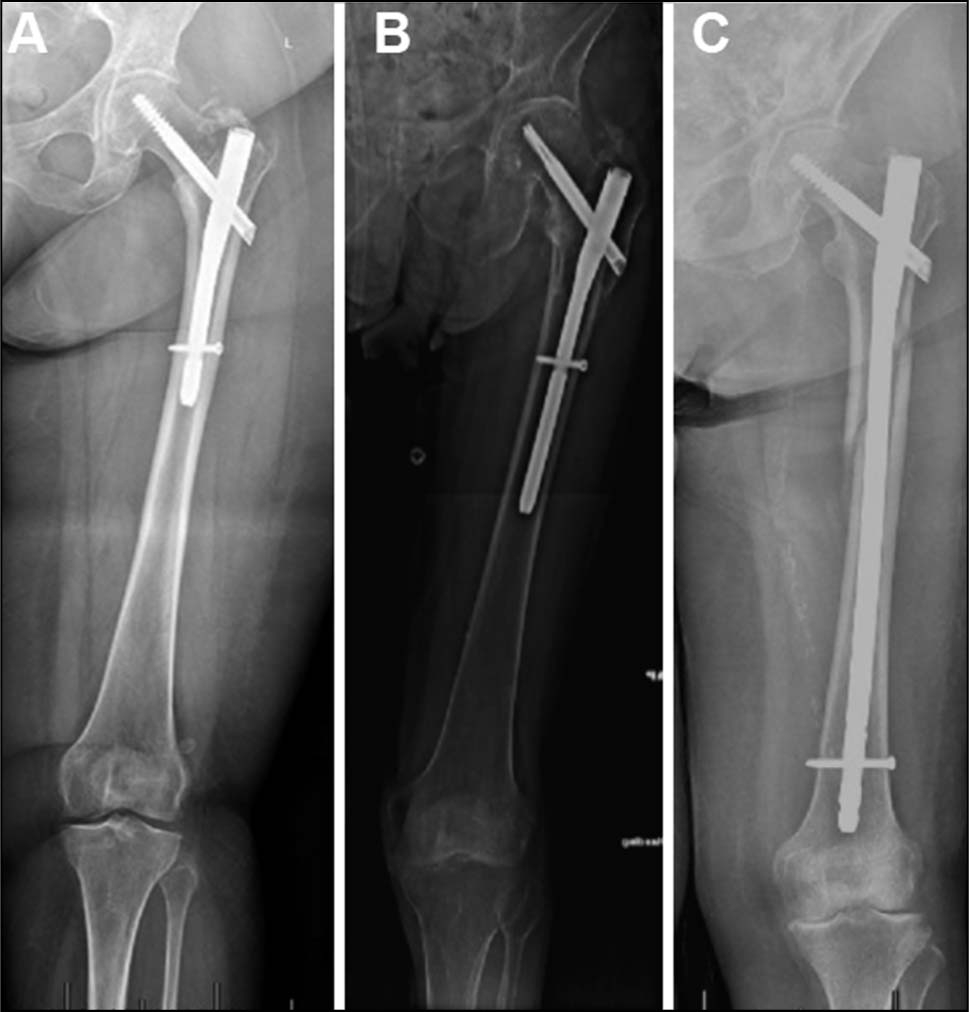

将锁定螺钉放置在动态位置(动态孔的中间),其在负重时允许骨折动态化。术后十二周的X射线图,显示骨折愈合进展和复位得以保持。